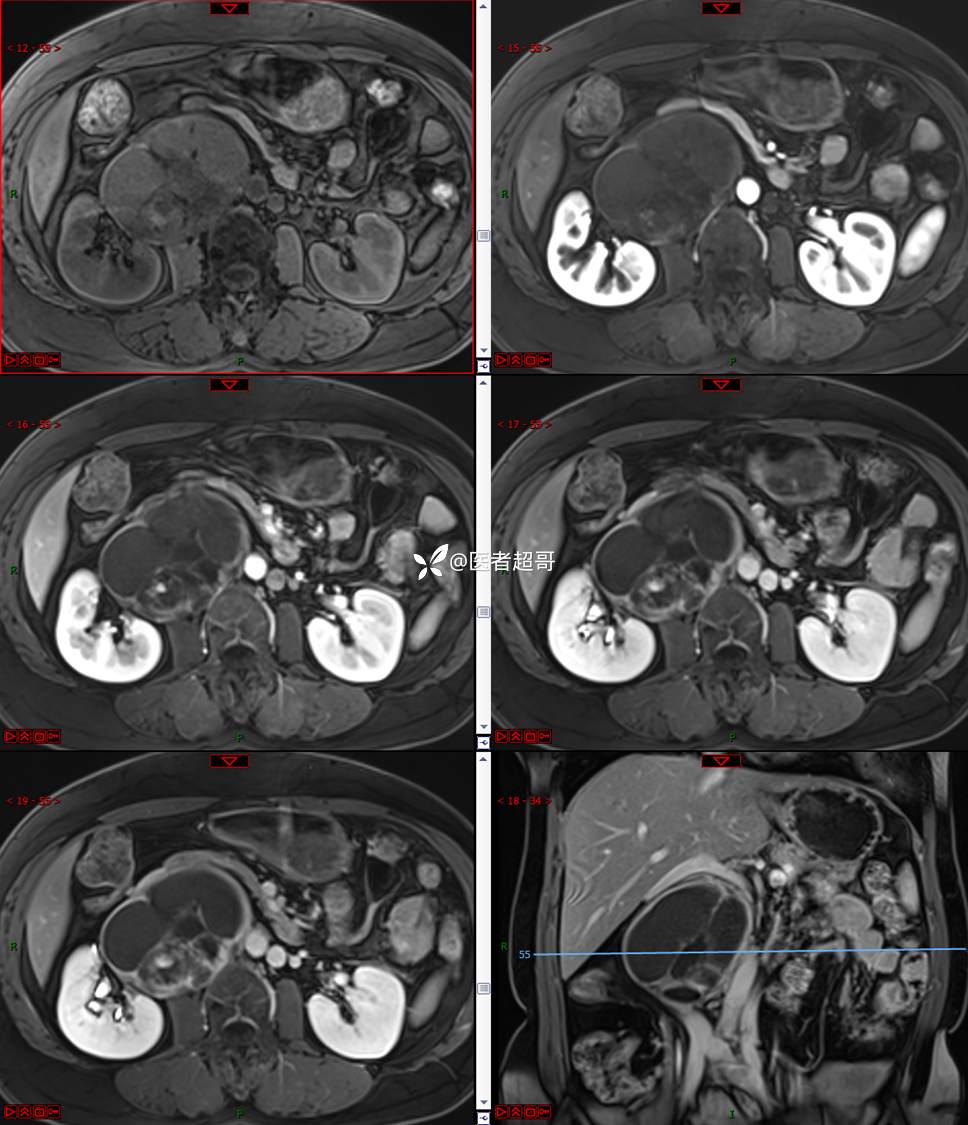

【影诊笔记671】定位有难度,究竟是腹腔内or腹膜后,请先定位,再定性!有结果~~~

hyy838 推荐女,52岁

主诉:查体发现腹部肿物1周。

现病史:患者1周前于我院查体发现右侧腹部肿物,无腹痛、腹泻、便血,无恶心、呕吐,患者为求进一步治疗,遂就诊于我院,门诊以“腹部肿物”收入院。患者自患病以来睡眠可,精神可,饮食可,小便无明显异常,体重无明显变化。

专科检查:腹部平坦,腹肌软,无压痛及反跳痛,无包块,肝脾无肿大,Murphy征阴性,腹部叩鼓,肝脾双肾无叩痛,移动性浊音阴性,肠鸣音正常。我院 肝胆胰脾肾彩超提示:脂肪肝、腹腔内囊实性团块,建议进一步检查。